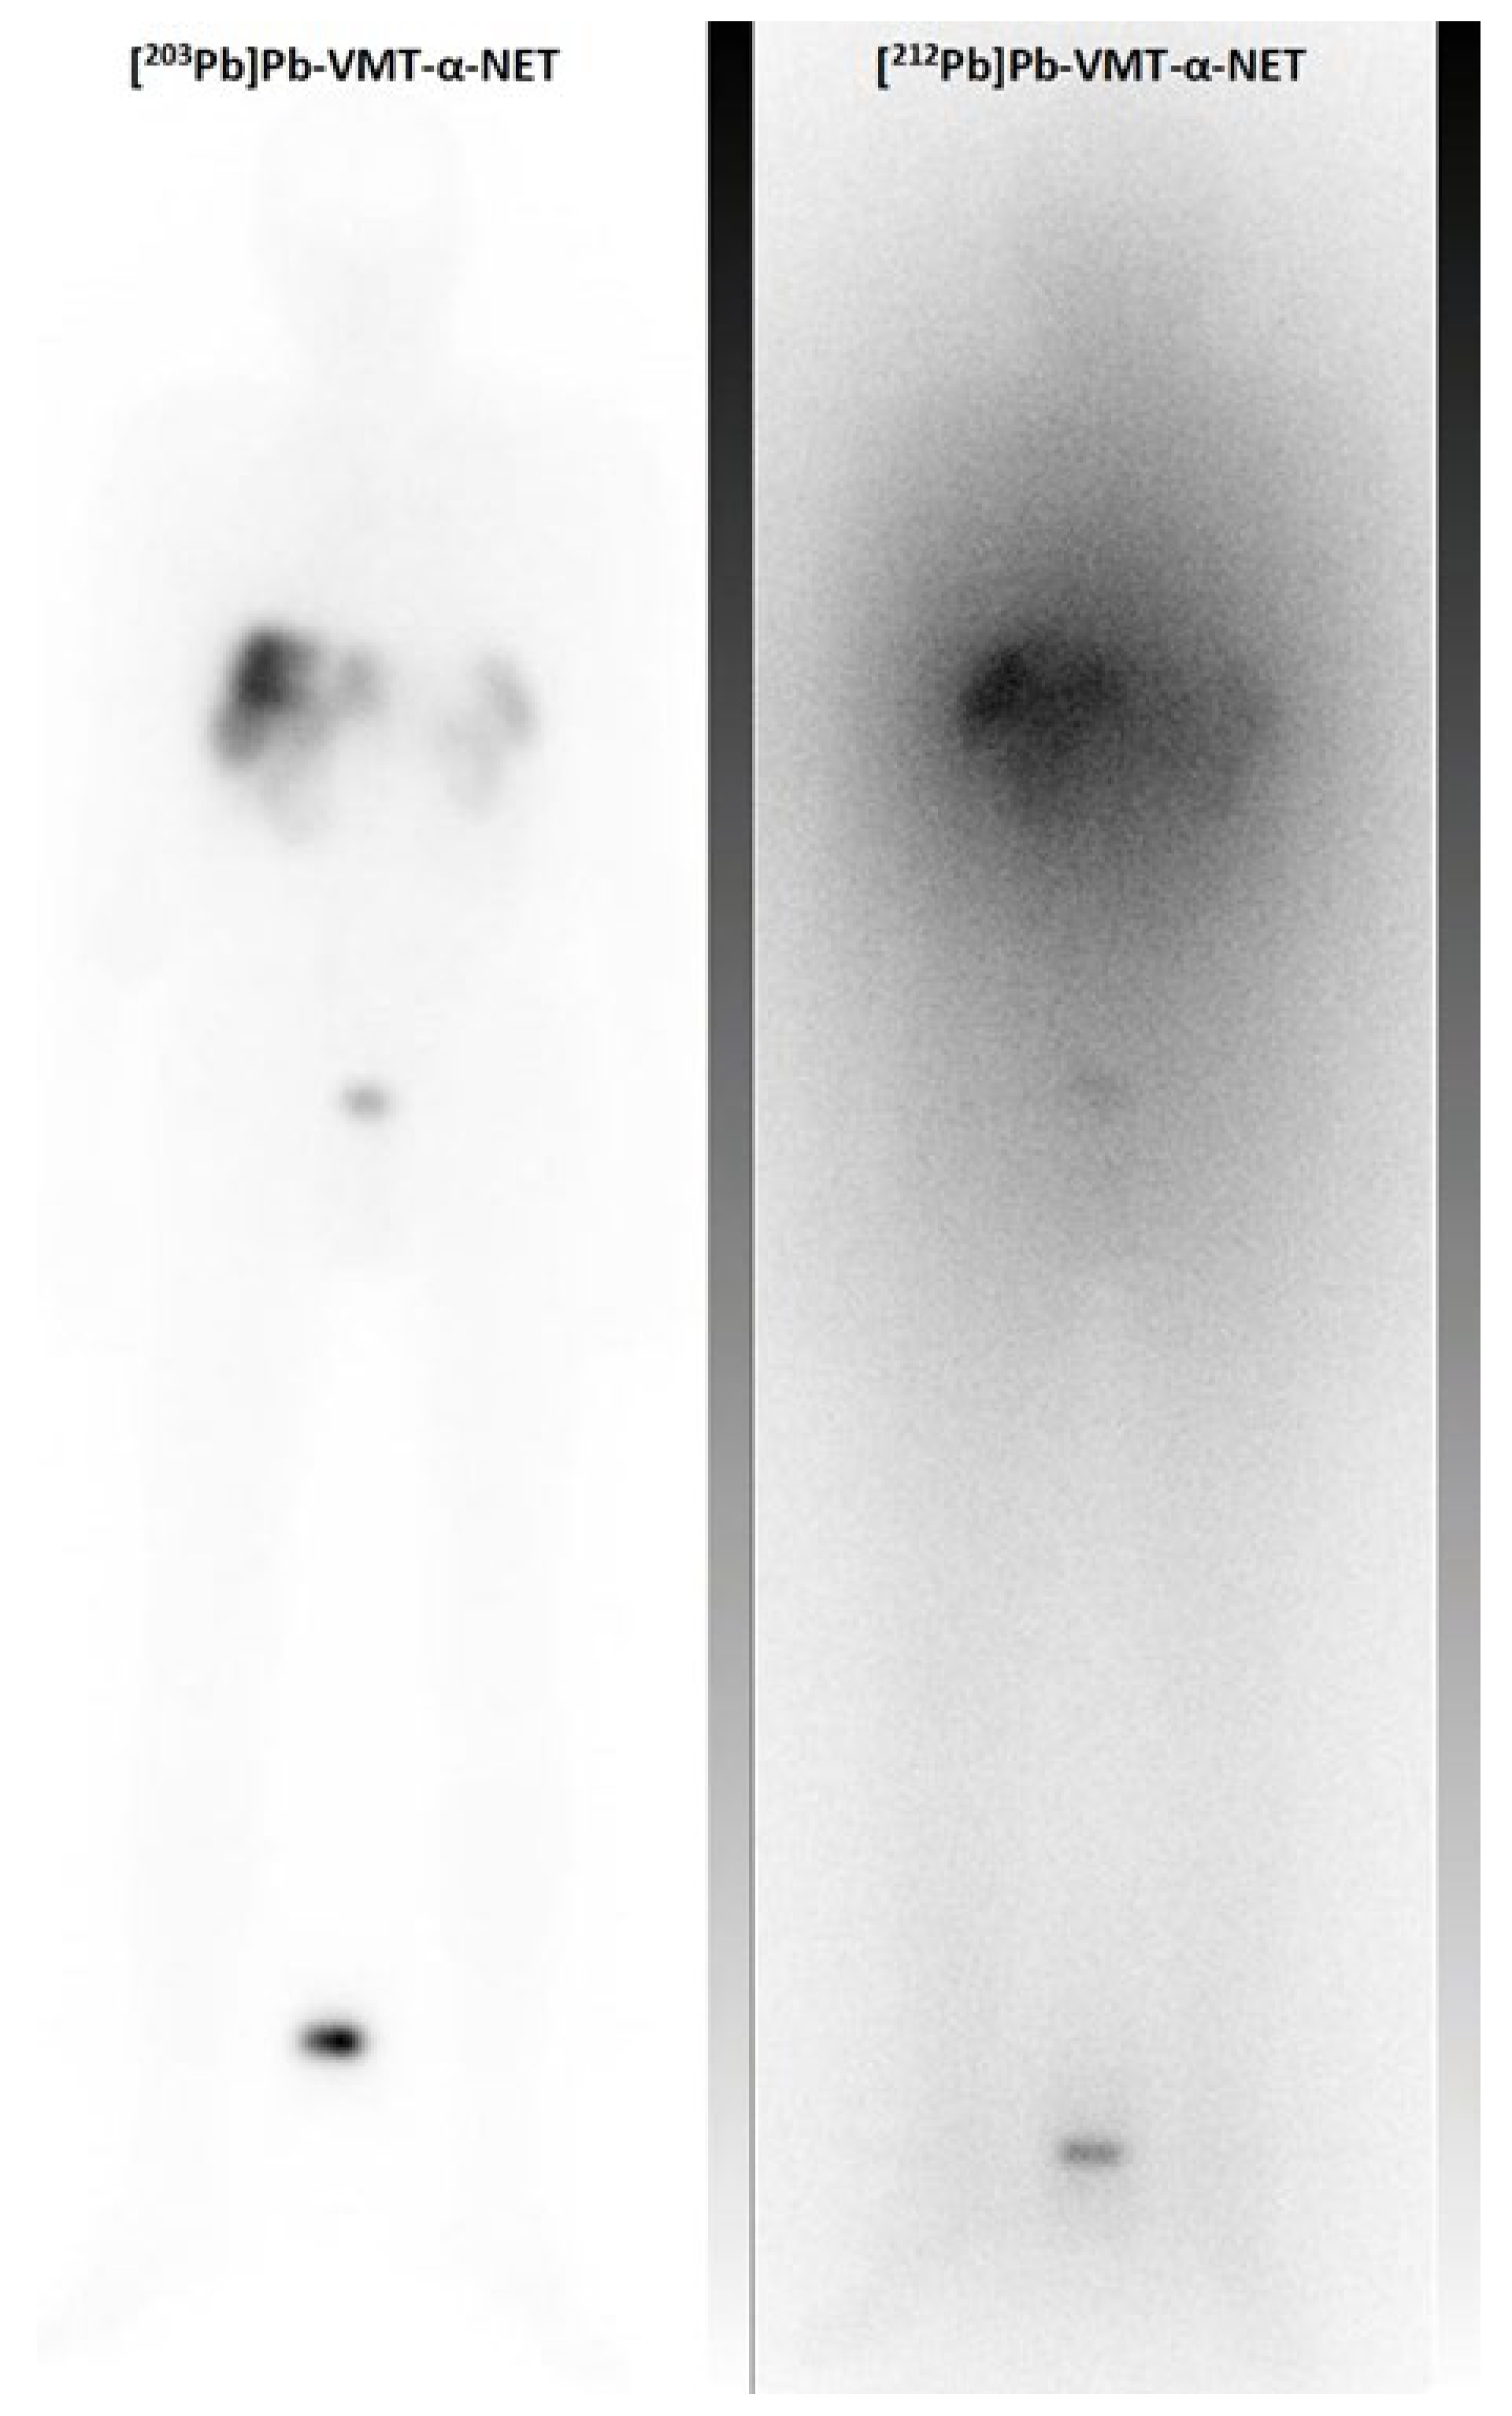

- Muller, D.; Herrmann, H.; Schultz, M.K.; Solbach, C.; Ettrich, T.; Prasad, V. 203Pb-VMT-alpha-NET Scintigraphy of a Patient With Neuroendocrine Tumor. Clin. Nucl. Med. 2023, 48, 54–55. [Google Scholar] [CrossRef] [PubMed]

- Michler, E.; Kastner, D.; Brogsitter, C.; Pretze, M.; Hartmann, H.; Freudenberg, R.; Schultz, M.K.; Kotzerke, J. First-in-human SPECT/CT imaging of [212Pb]Pb-VMT-alpha-NET in a patient with metastatic neuroendocrine tumor. Eur. J. Nucl. Med. Mol. Imaging 2023. [Google Scholar] [CrossRef] [PubMed]